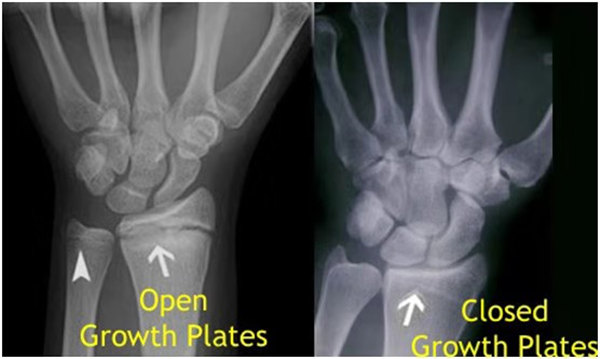

我們都知道,人體的高矮是由骨骼的生長(zhǎng)發(fā)育決定的,特別是下肢長(zhǎng)骨。長(zhǎng)骨呈長(zhǎng)管狀,在長(zhǎng)骨的兩端有一種專管骨骼生長(zhǎng)的骺軟骨,它與干骺端之間有一盤狀軟骨結(jié)構(gòu)稱為骺板(線),在幼兒的X光片上表現(xiàn)為一條較寬的透光帶。 (見下圖)

未成年時(shí)隨著年齡的增加骺軟骨端不斷骨化,骨骼就不斷增長(zhǎng)。當(dāng)骨骺線完全閉合時(shí)骨骼就停止生長(zhǎng),個(gè)子也就不再增長(zhǎng)了。一般骨骺端完全閉合的年齡是18~20歲左右。